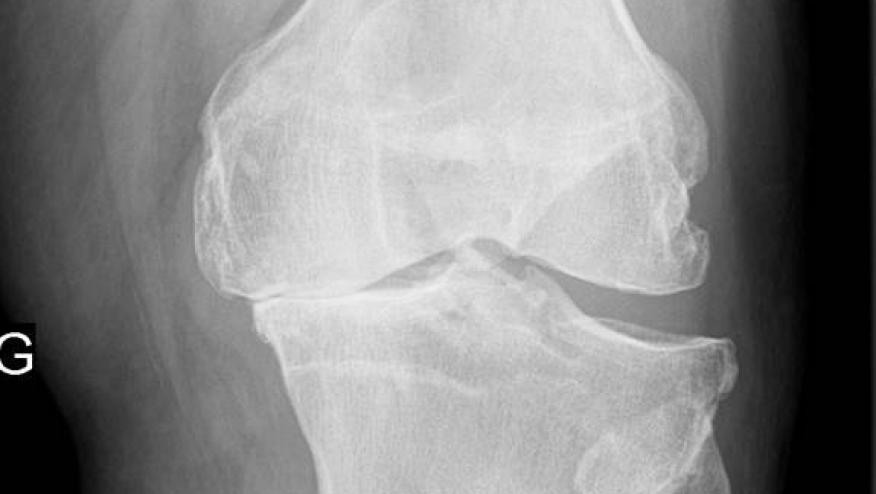

What’s new in knee osteoarthritis that matters? Save